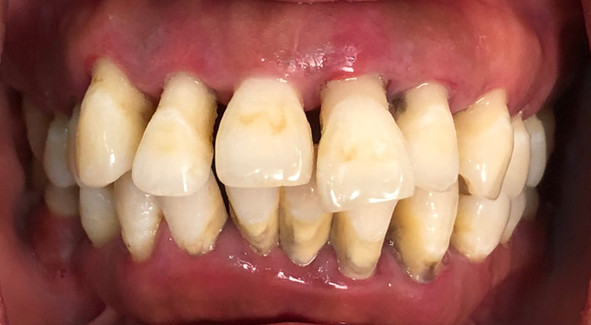

遗憾的是当时S小姐的每一颗牙齿都已经处于摇摇欲坠的状态了,牙槽骨严重萎缩,并有较严重的牙周炎,影响了牙龈的颜色和口气。这导致简单的牙齿矫正或者牙齿贴片等传统的笑容改造项目已经无法帮助到她,她即将面对的是全口拔牙后进行牙齿种植,以达到全口重建的目的。

面诊当天牙齿照片-09/2018